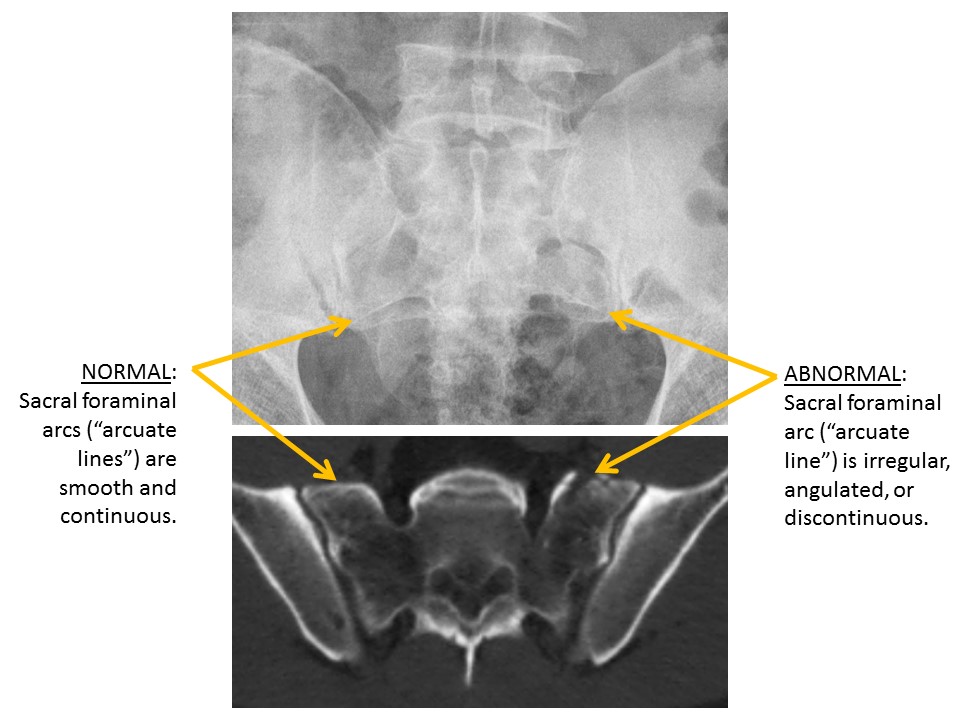

SACRUM and SACROILIAC JOINTS

There are displaced fractures or disrupted/asymmetric foraminal arcs. [Yes/No]